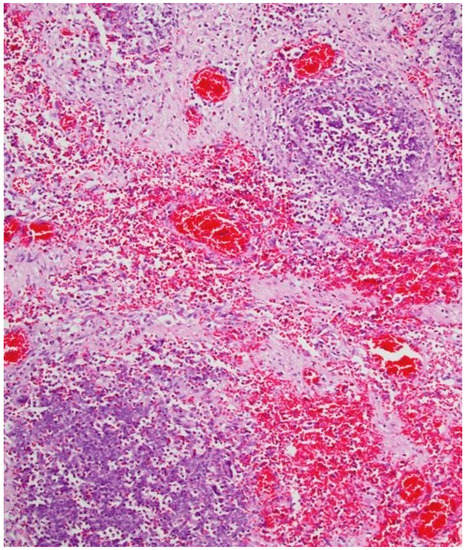

The autopsy evidenced the following: congestion of meningeal vessels; oedema and congestion of both lungs; left ventricular hypertrophy with widespread congestion and sclerosis of both valves and coronaries; inflammation of small intestine and stomach, both presenting a greenish liquid with a very intense smell (see Figure 1); congestion of spleen and kidneys.

Figure 1. Internal stomach walls with areas of inflammation.